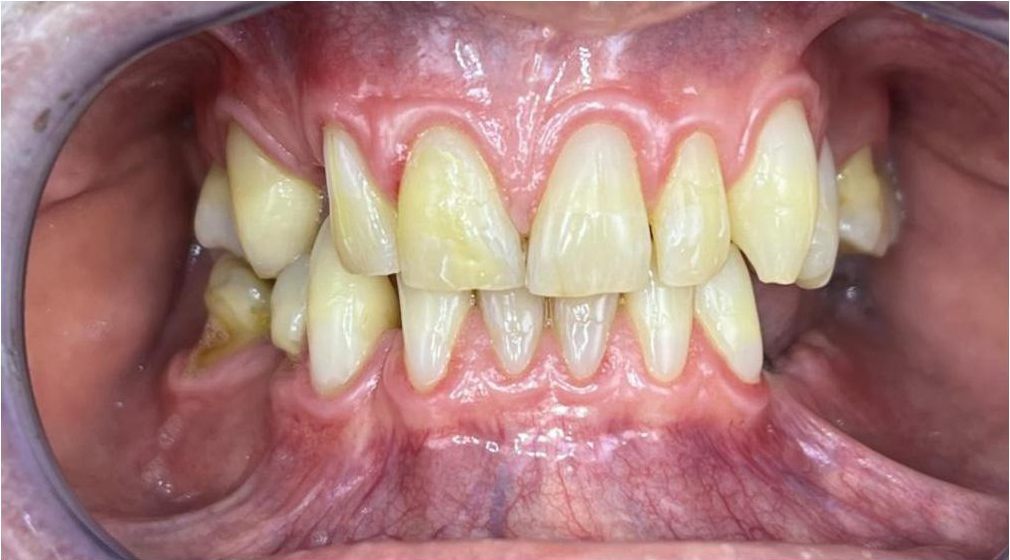

Pomimo zaleceń dr do wdrożenia również leczenia ortodontycznego, Pacjentka, znając wszystkie wady i zalety bezwzględnie zdecydowana zakamuflować stłoczenia, nieprawidłowości kontaktów, płaszczyzny zgryzowe, tylko i wyłącznie protetycznymi rozwiązaniami. Dr Joanna ustaliła z Pacjentką pod Jej wymagania wspólny plan działań. Wybierając takie rozwiązanie lekarz i laboratorium ma zawsze utrudnienie, by jaknajbardziej harmonijnie zaplanować projekt uśmiechu.

Dzięki precyzyjnej diagnostyce, doktor Magdalena Zawirska opracowała kompleksowy plan leczenia, który obejmował: stomatologię zachowawczą, periodontologię i protetykę stomatologiczną. Zastosowano licówki i korony pełnoceramiczne, przeprowadzając kompleksową rekonstrukcję zwarcia.